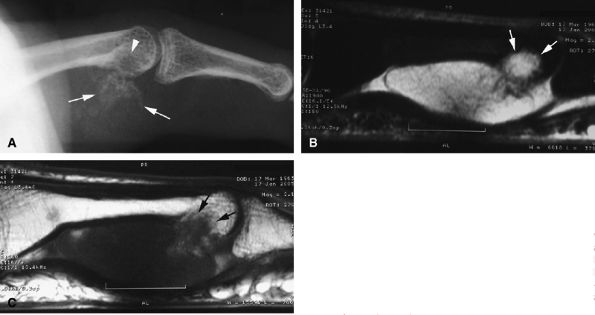

FIGURE 11.31 ● Mallet finger. (A) Fracture avulsion (arrow) of the base of the distal phalanx (lateral view). (B) Sagittal T1-weighted images in a different case showing a tear of the terminal band of the extensor apparatus (arrows) with thickening of soft tissues. There is bone edema (arrowhead) of the base of the distal phalanx without fracture.

FIGURE 11.47 ● Jersey finger. (A) Sagittal T2-weighted image. (B) Coronal post-contrast T1-weighted images. (C) Axial T1-weighted image. Distal avulsion of the FDP tendon is shown with the proximal end (white arrows) at the metacarpophalangeal joint (type I). The tendon is wavy in the palm (arrowheads). The empty digital canal (in C) may mimic a remnant tendon, but the FDS tendon (asterisk) is alone in the canal.